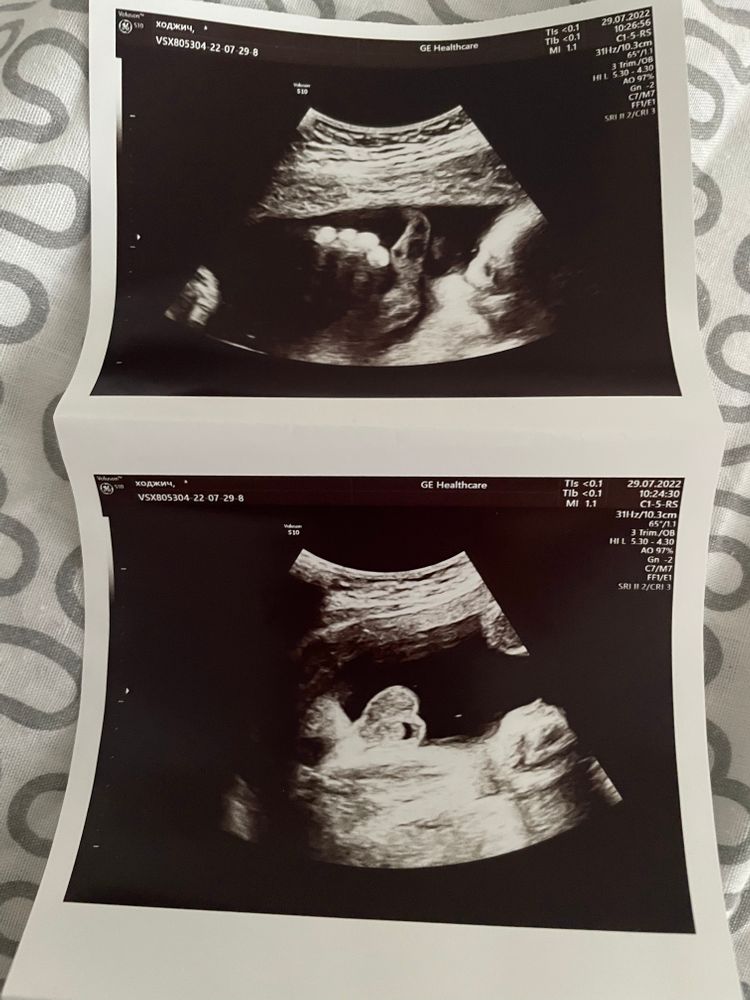

УЗИ, КТГ, доплерДевочки, всем привет 👋. Сделали третье УЗИ на 31 недели, сейчас хотели с мужем в альбом беременности приклеить снимки с УЗИ, но никак не разберем, что и где?!))) Кто разбирается и может помочь, осчастливьте, пожалуйста, нас слепых 😅

Я только на первом фото увидела пальцы руки))) На остальных непонятно что)))

1 фото пальчики (не понятно ручки или ножки)

2 фото похоже на яички и мошонку

4 как будто профиль лица, но такое неудачное

Эти снимки со скрининга? Вы сказали третье узи. Если это сл скрининга, то Вы там можете вообще не увидеть ребенка. Врачи же смотрят в основном на этом сроке внутренние органы как сформировались.